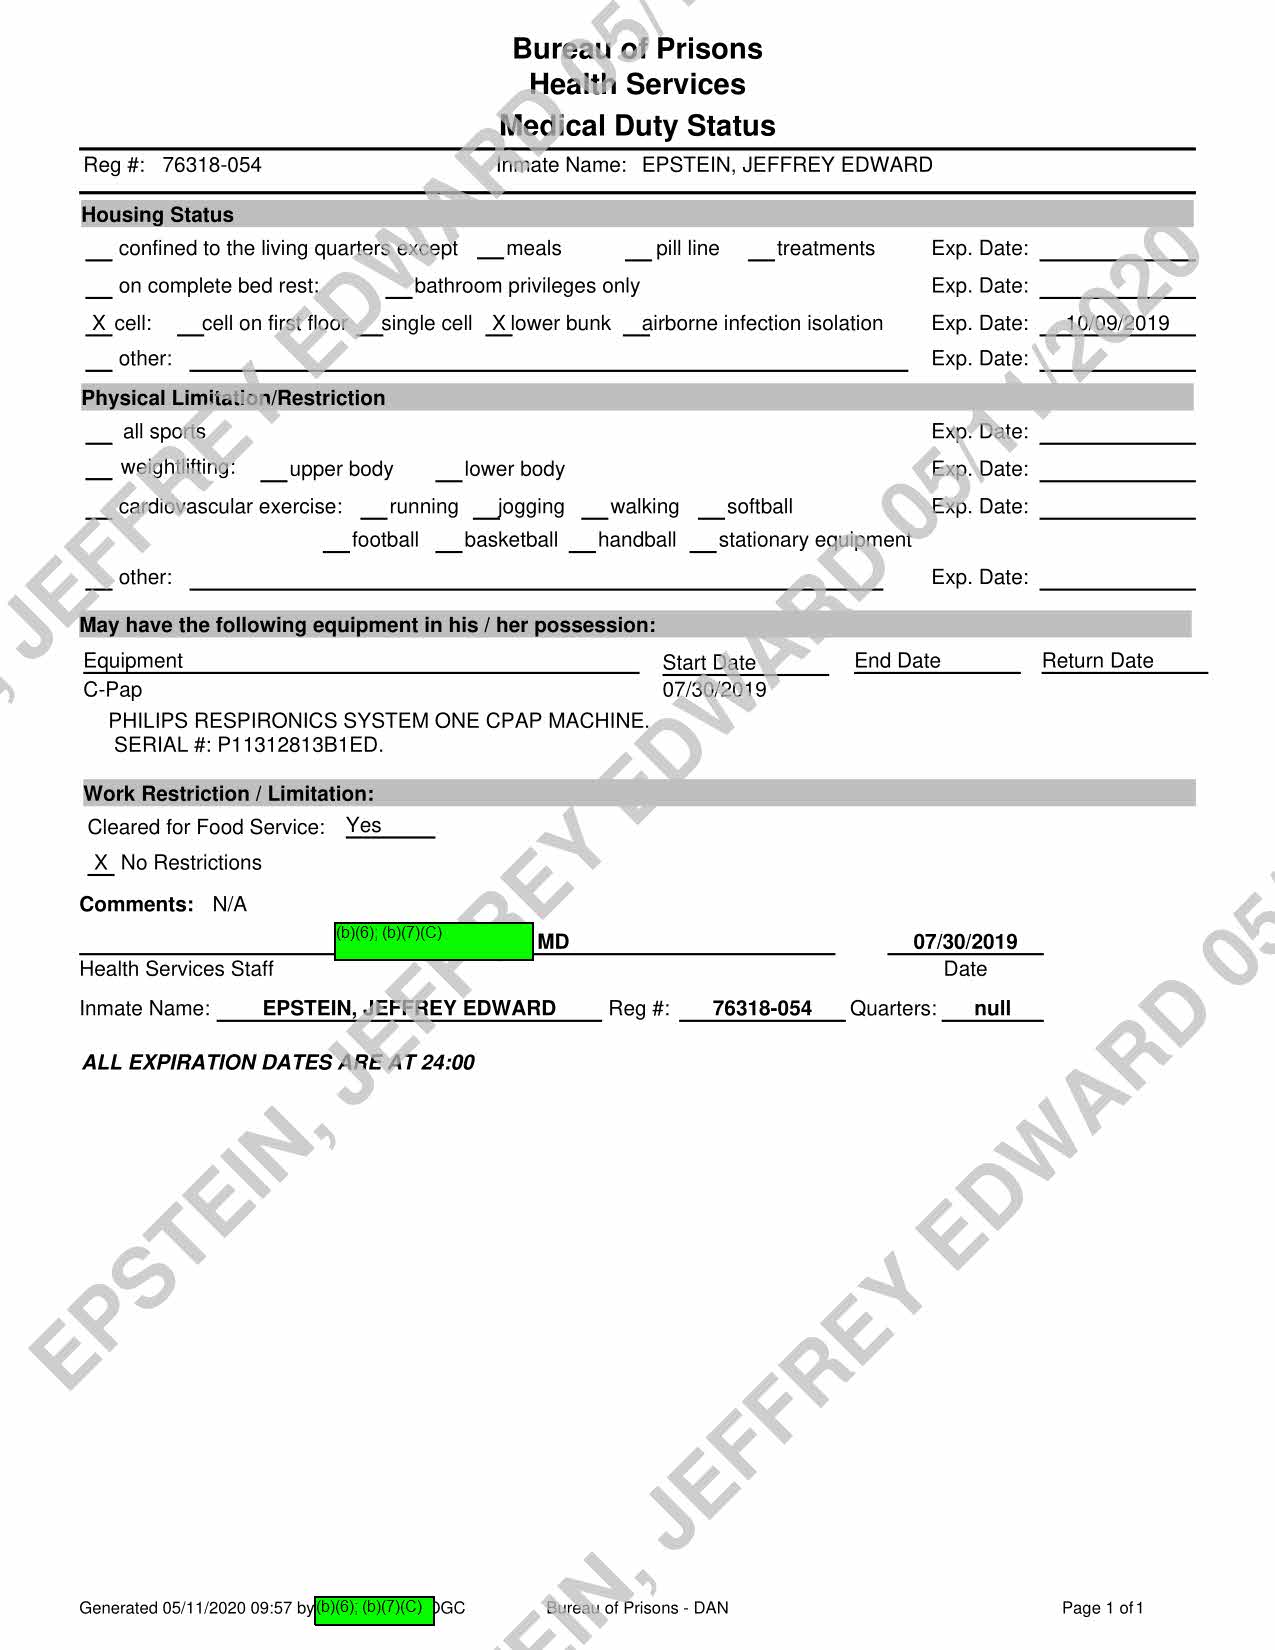

Fwd: Jeffrey Epstein, 76318-054 From b)(6); (b)(7)(C) To Executive Stafff._b_X5_>;_<b_X7_><_c> ______ __. Date Subject: Attachments: Good morning all, b)(6); (b)(7)(C) 2019/07/26 10:10 Fwd: Jeffrey Epstein, 7 6318-054 TEXT.htm Epstein's attorneys are trying to get him his CPAP machine per our request. Can we have them hand-deliver it to medical staff as we have in previous instances? Thank ou, b)(6); (b)(7)(C) > > ~ b)(6); (b)(7)(C) Mr. }~i~,., I l@gmail.com> 7/26/2019 9:50 AM > > > Is Mr. Epstein approved to receive a CPAP machine? If so, should we send it directly to him through the inmate mail system? Please confirm. Thank you. b)(6); (b)(7)(C) Page 747